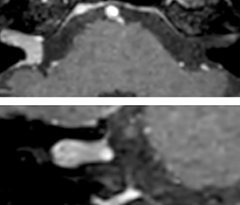

In this patient with acute right motor deficit and aphasia, the b2000 diffusion weighted image is normal. The SWIp image demonstrates more prominent veins in the right hemisphere, which could reflect increased deoxyhemoglobin contents. Fast ASL shows low CBF regions in the left frontal lobe. A follow-up ASL after one hour demonstrates high CBF values in the same area. The final diagnosis was migraine with aura.